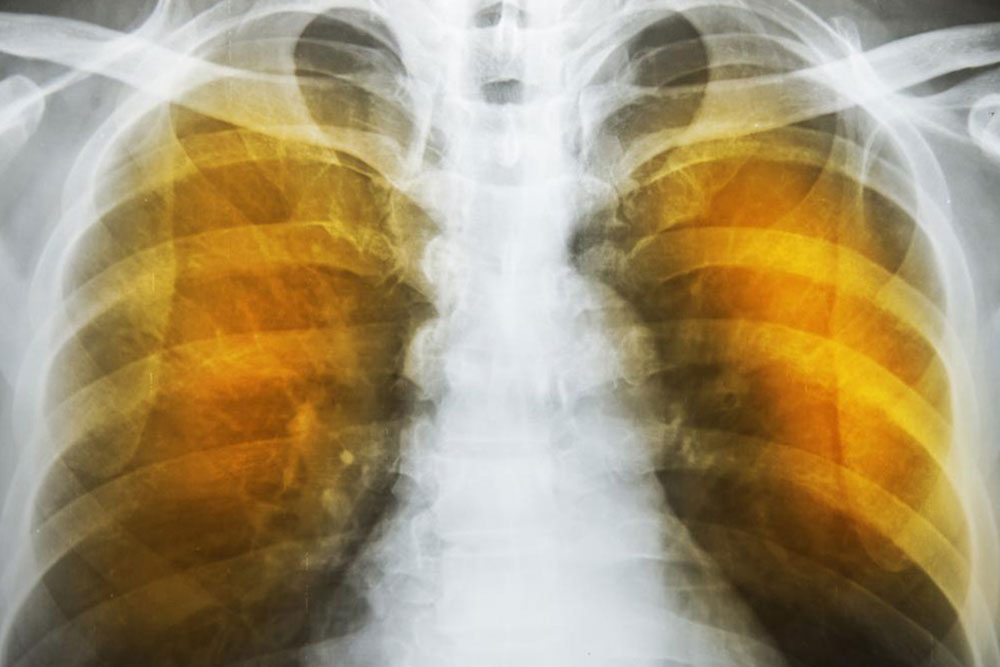

Emphysema is an oppressive respiratory disorder which results from the disintegration of the alveoli, i.e., the tissues where the interchange of gas with blood takes place. Destruction in any large scale will reduce the gas transfer area and the process of gas transfer itself, leading to oxygen starvation or hypoxia. When conventional treatment with bronchodilators, corticosteroids etc. have ceased to give relief, one has to resort to a method known as Long Term Oxygen Therapy or LTOT.

Another complication is the alveoli becoming weaker, and then starting to break. When this assumes larger scale, vacant spaces are formed called bullae. This reduces the gas transfer area as well as the capacity of the lung to expand. These are often have to be surgically removed to allow more space for the lung to expand. In the ultimate case, lung transplant becomes the only choice. Another scenario is a large-scale disintegration of alveoli that can cause pneumothorax, which is a condition in which the chest cavity is filled with air and the lungs collapse. This is a very serious condition if not fatal.